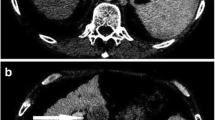

HCCs are generally arterial hypervascular tumors. However, hyperenhancement (“wash-in”) in the arterial phase alone is poorly specific for HCC. When hypoenhancement in the portal venous or delayed phases (“wash-out”) is added, both the specificity and sensitivity increase (Fig. 5.1) [8]. Early HCCs are, however, characterized by a hypo- or isoenhancement in arterial phase imaging, due to their incomplete neoangiogenesis [7]. Another characteristic imaging feature included by LI-RADS among the major criteria for HCC diagnosis is the presence of a peripheral “capsule appearance”, histologically composed also by fibrous tissue, which explains its late enhancement due to retention of gadolinium in the extracellular interstitial spaces [6, 9]. Another characteristic feature of HCC, included in the “ancillary criteria” of LI-RADS, is the “nodule-in-nodule” appearance (Fig. 5.2) [10]. Vascular invasion is more frequent in progressed HCC. It can be microvascular, if it is only appreciable on microscopy, or macrovascular (Figs. 5.3 and 5.4) which refers to macroscopically visible tumor in vein (LR-TIV) [11]. Both of them are indicators of a poor overall survival and an aggressive biologic behavior [6]. The presence of intralesional fat is very specific for HCC and this is well evaluable on MRI T1-weighted GRE dual-echo sequences, with loss of signal in the out-of-phase images (Fig. 5.5) [10].

A voluminous lesion subverts the structure of the right liver, with imaging compatible with hepatocellular carcinoma appreciable on the CT axial images in the arterial (a), portal venous (b) and delayed (c) phases. Macrovascular invasion is observed with neoplastic thrombosis causing occlusion of the right portal vein, subocclusion of the left portal vein and the common portion of the mesenteric splenic confluence (black arrow). The figure is published with the patient’s authorization